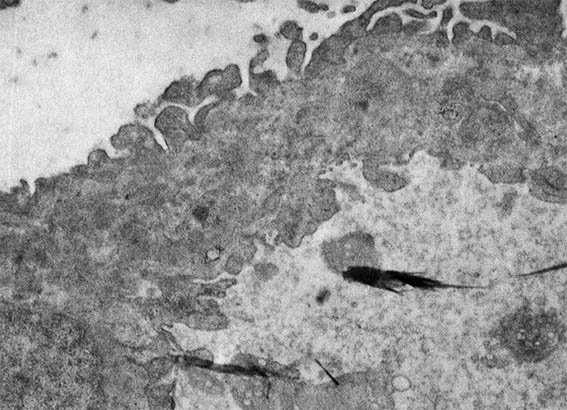

Figure 11. Electron microscopy, original magnification, X4,000. Note extensive podocyte damage, severe thickening of capillary walls, endothelial cell enlargement, and electron-dense subendothelial areas.